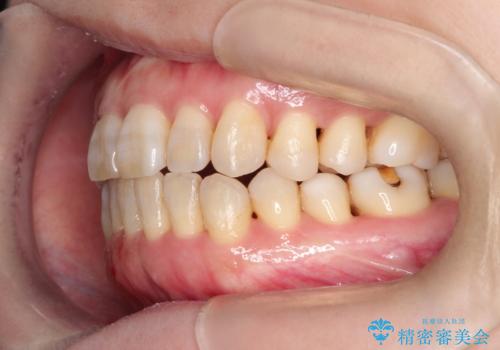

マウスピース枚数 初回36枚 + 追加26枚

概ね1年4ヶ月で治療完了しました。

マウスピース矯正は開咬(オープンバイト)に対して有利な治療メカニクスを持ちます。

当院独自の工夫を随所に盛り込み、狙い通りの治療結果が得られました。